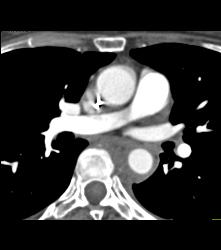

Intramural Hematoma